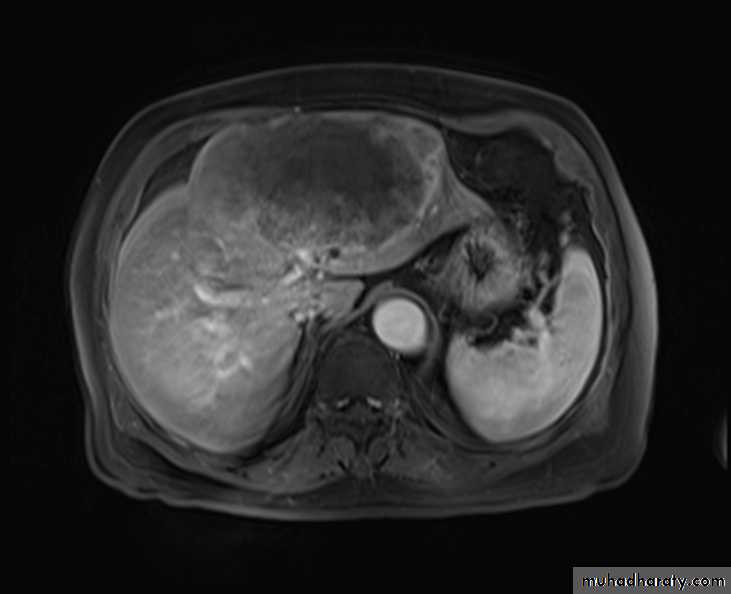

MRI

Benign lesions

Hemangioma